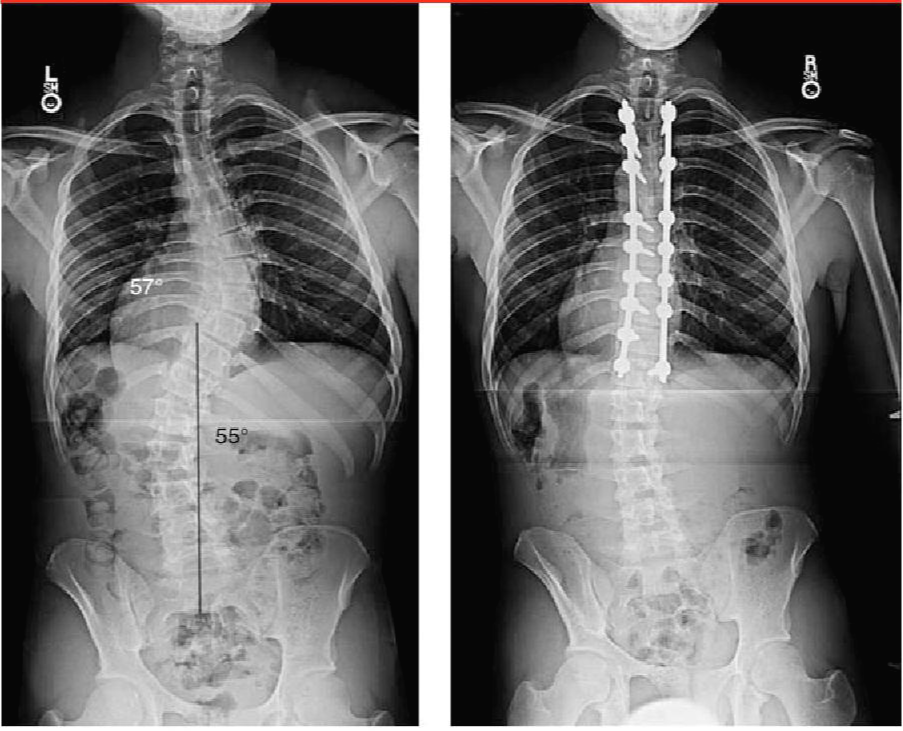

척추가 이렇게 휘게 되면 일상생활에 지장이 없는 경우는 많습니다. 하지만 만곡이 심해지는 경우 심폐합병증이 가장 치명적이고 무서운 합병증이 될 수 있습니다. 일단 기본적으로 whole spine X-ray 를 촬영하여 척추의 pedicle 의 회전과 만곡의 정도를 cubbs angle 등으로 측정을 하게 됩니다.

척추 측만증에서 수술을 하게 되면 fusion 을 주로 하게 됩니다.

척추측만증 교정원칙

주만곡을 꼭 모두 유합을 해야하며, 유연성이 있는 보상성 만곡은 유합할 필요가 없습니다.

만곡 상부의 neutral vertebra 부터 하부의 neutral vertebra 까지 유합을 합니다. 따라서 척추체의 회전의 유무가 중요하게 됩니다.

유합의 가장 하단은 stable vertebra 로 sacral central line이 가운데를 지나가도록 해야합니다.

흉추의 후만 및 요추의 전만각은 정상에 가깝게 교정해야합니다.